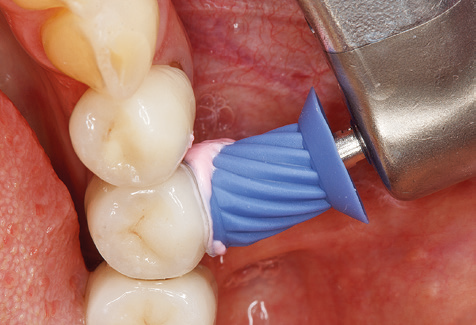

Una buona illuminazione del campo di lavoro facilita notevolmente il processo. Il sistema utilizzato dagli autori ottiene questo risultato grazie a un anello LED 5x integrato nel manipolo. Naturalmente, viene offerta anche una serie di consigli di lavoro per diverse indicazioni. Un inserto diritto, utilizzabile universalmente, è lo strumento di base necessario per la pulizia meccanica dei denti naturali (Fig. 5a e b). Sono disponibili anche inserti curvi, che consentono l'accesso alle forcazioni esposte, per le aree difficili da raggiungere nella regione posteriore (Fig. 6).

Naturalmente, anche i consigli di lavoro per la pulizia delle superfici degli impianti sono indispensabili per SPT nei pazienti dotati di impianti. L'inserto per la pulizia dell'impianto in questo casoi è caratterizzato dal suo design affusolato ed esagonale. Questo design consente una penetrazione leggera e atraumatica nella tasca perimplantare e mostra buone prestazioni di pulizia (Fig. 7).

Fig. 4: Sonde flessibili con marcature millimetriche sono consigliate per il sondaggio di impianti dentali (ad es. Colorvue Kit PCV11KIT6, HuFriedy). - Fig. 5a e b: Un inserto diritto (1P, W&H Dentalwerk Bürmoos GmbH) è uno strumento adatto per l'uso su tutti i denti naturali. - Fig. 6: Inserti curvi (3Pr / 3Pl, W&H Dentalwerk Bürmoos GmbH) si prestano alla lavorazione di aree difficili da raggiungere del dente e delle superfici radicolari (ad es. Forcazioni). - Fig. 7: L'inserto esagonale conico per la pulizia dell'impianto (1I, W&H Dentalwerk Bürmoos GmbH) consente una pulizia atraumatica ed efficace della superficie della corona e del moncone. - Fig. 8: Le curette in titanio e carbonio sono strumenti adatti per la pulizia manuale delle superfici dell'impianto.